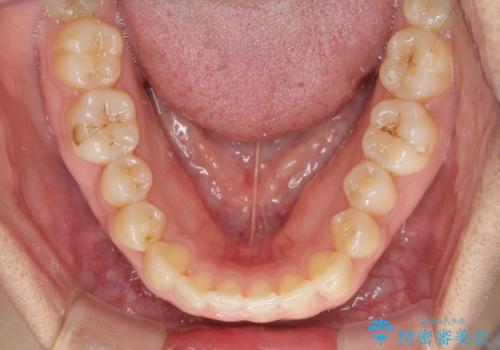

- 上下のデコボコを改善したいとのことで来院された患者様です。

近々妊娠する予定であり、極力短期間で治療したいとのことで、ワイヤー装置による非抜歯矯正治療を行うこととしました。